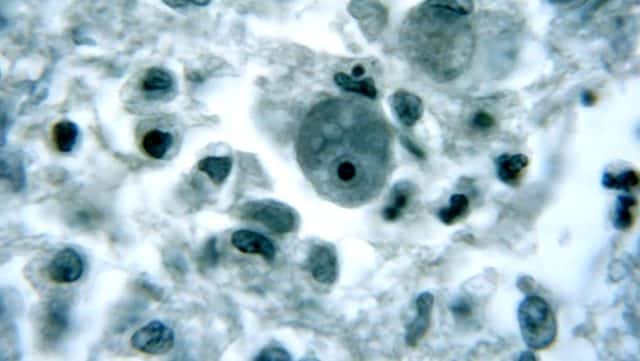

Tek hücreli amip, beyinde enfeksiyon görülmesine neden oluyor ve vakalar çoğunlukla ölümcül duruma geliyor. Genelde göl ve nehir gibi tatlı sularda yer alan ve tek hücreli Naegleria fowleri, yalnızca burun ile bulaşıyor ve insandan insana bulaşı bulunmuyor.

Uzmanlar, hızlı bir şekilde beyin dokusuna zarar veren Naegleria fowleri'nin jeotermal sularda ve iyi klorlanmamış havuz sularında da yer alabileceğini belirtiyor. Naegleria fowleri'nin yutulması durumunda hastalığa yol açmadığı ifade ediliyor.